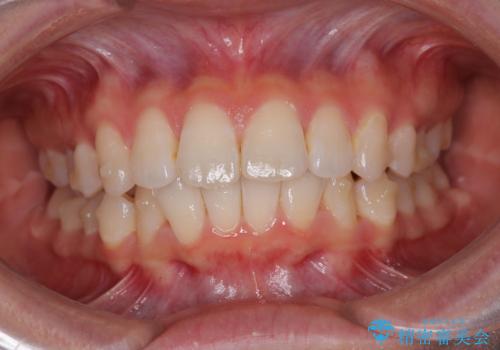

深い咬み合わせによる隙間 インビザライン矯正でコンプレックスを改善

- 上の前歯の隙間を気にして来院された患者様です。

インビザラインにより、上下の歯列を側方に拡大しつつ、前歯の隙間を閉じていくこととしました。

隙間の原因は強い咬合力や舌の突出癖、小帯の異常付着などがありますが、舌のトレーニングをしっかりと行いながら、装着時間を遵守して装着していただいたおかげで、スムーズに治療を終えることができました。